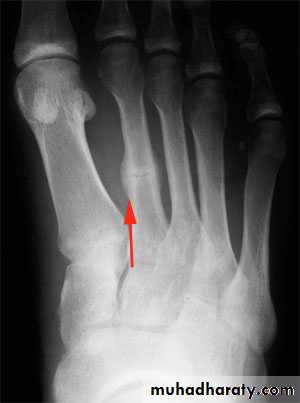

Fracture base of 5th metatarsal

This injury is very common, caused by foot torsion. It is nearly always caused by a twisting injury in which the foot is forced into inversion and equines (planter flexion), the styloid process at the base of the 5th metatarsal being pulled off by the tendon of the peroneus brevis muscle, which is inserted into it . There is pain and tenderness over lateral side of foot. It regarded as muscle injury. Treated by pressure bandage and analgesia, if pain sever a below-knee walking plaster for 3 weeks.